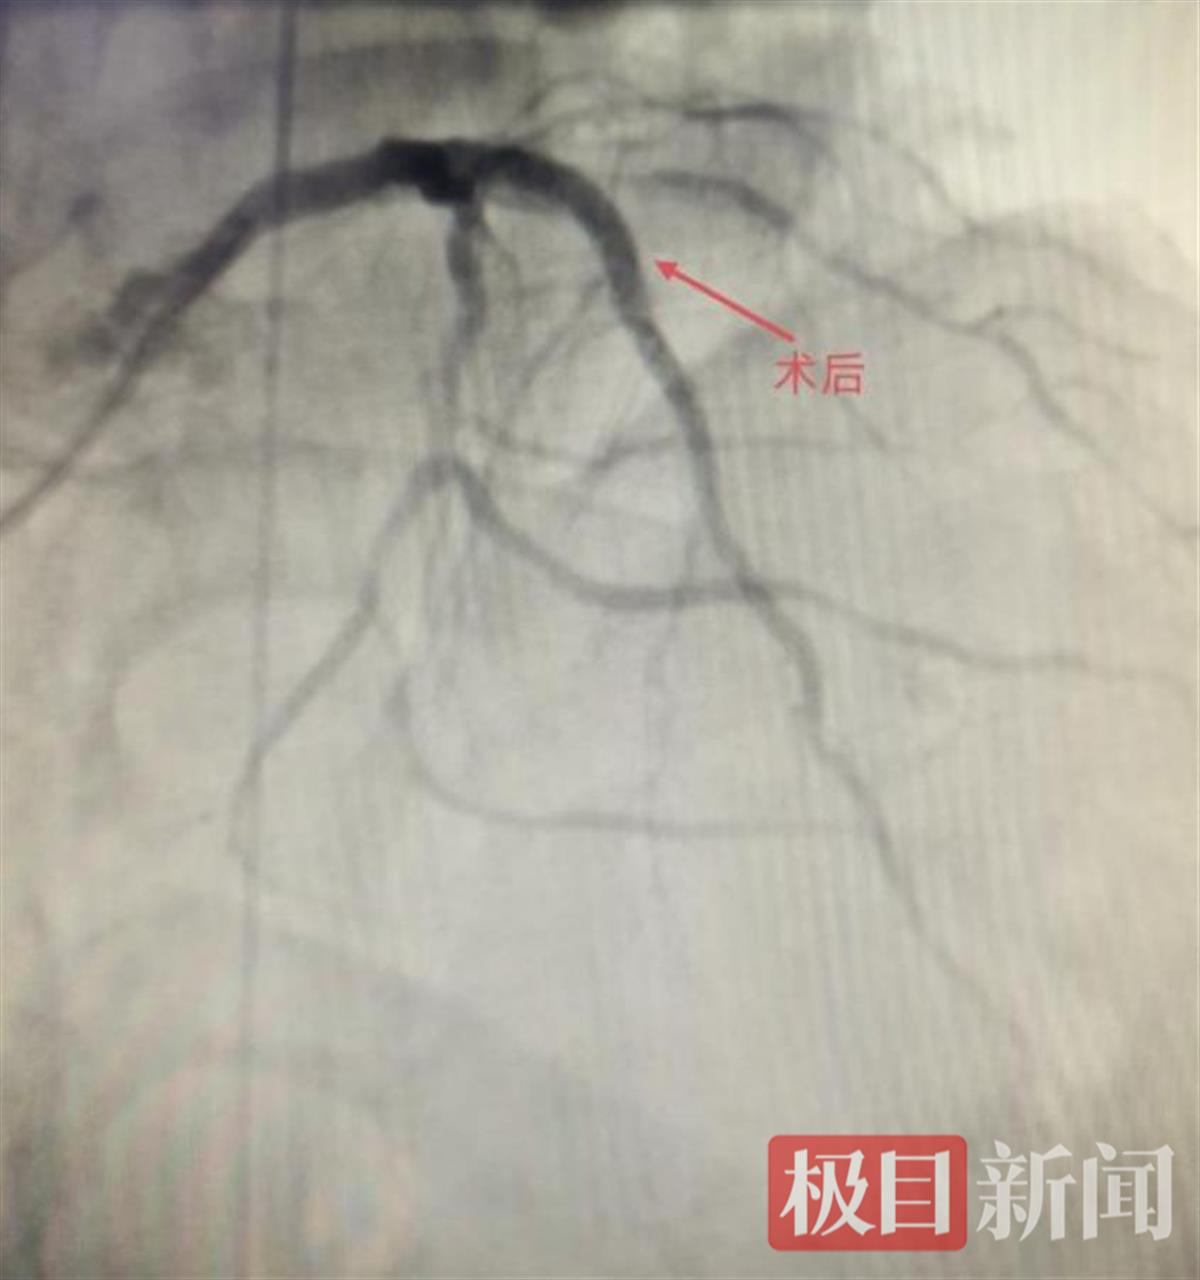

术后影像图

征得家属同意后,心血管内科主任医师胡家顺带领医疗团队,为爹爹进行手术。在球囊反搏的支持下,胡家顺带领手术团队成功地将支架植入到爹爹阻塞的冠状动脉中,恢复了血液的正常流通。当手术成功的消息传来,张爹爹的家人喜极而泣。术后,爹爹被送入心血管内科重症监护室进行密切观察和护理,在医护人员的精心照料下,他的情况越来越好,术后第三天便顺利出院。如今,他不仅能够独立行走、生活自理,还能进行日常活动,又能享受天伦之乐。